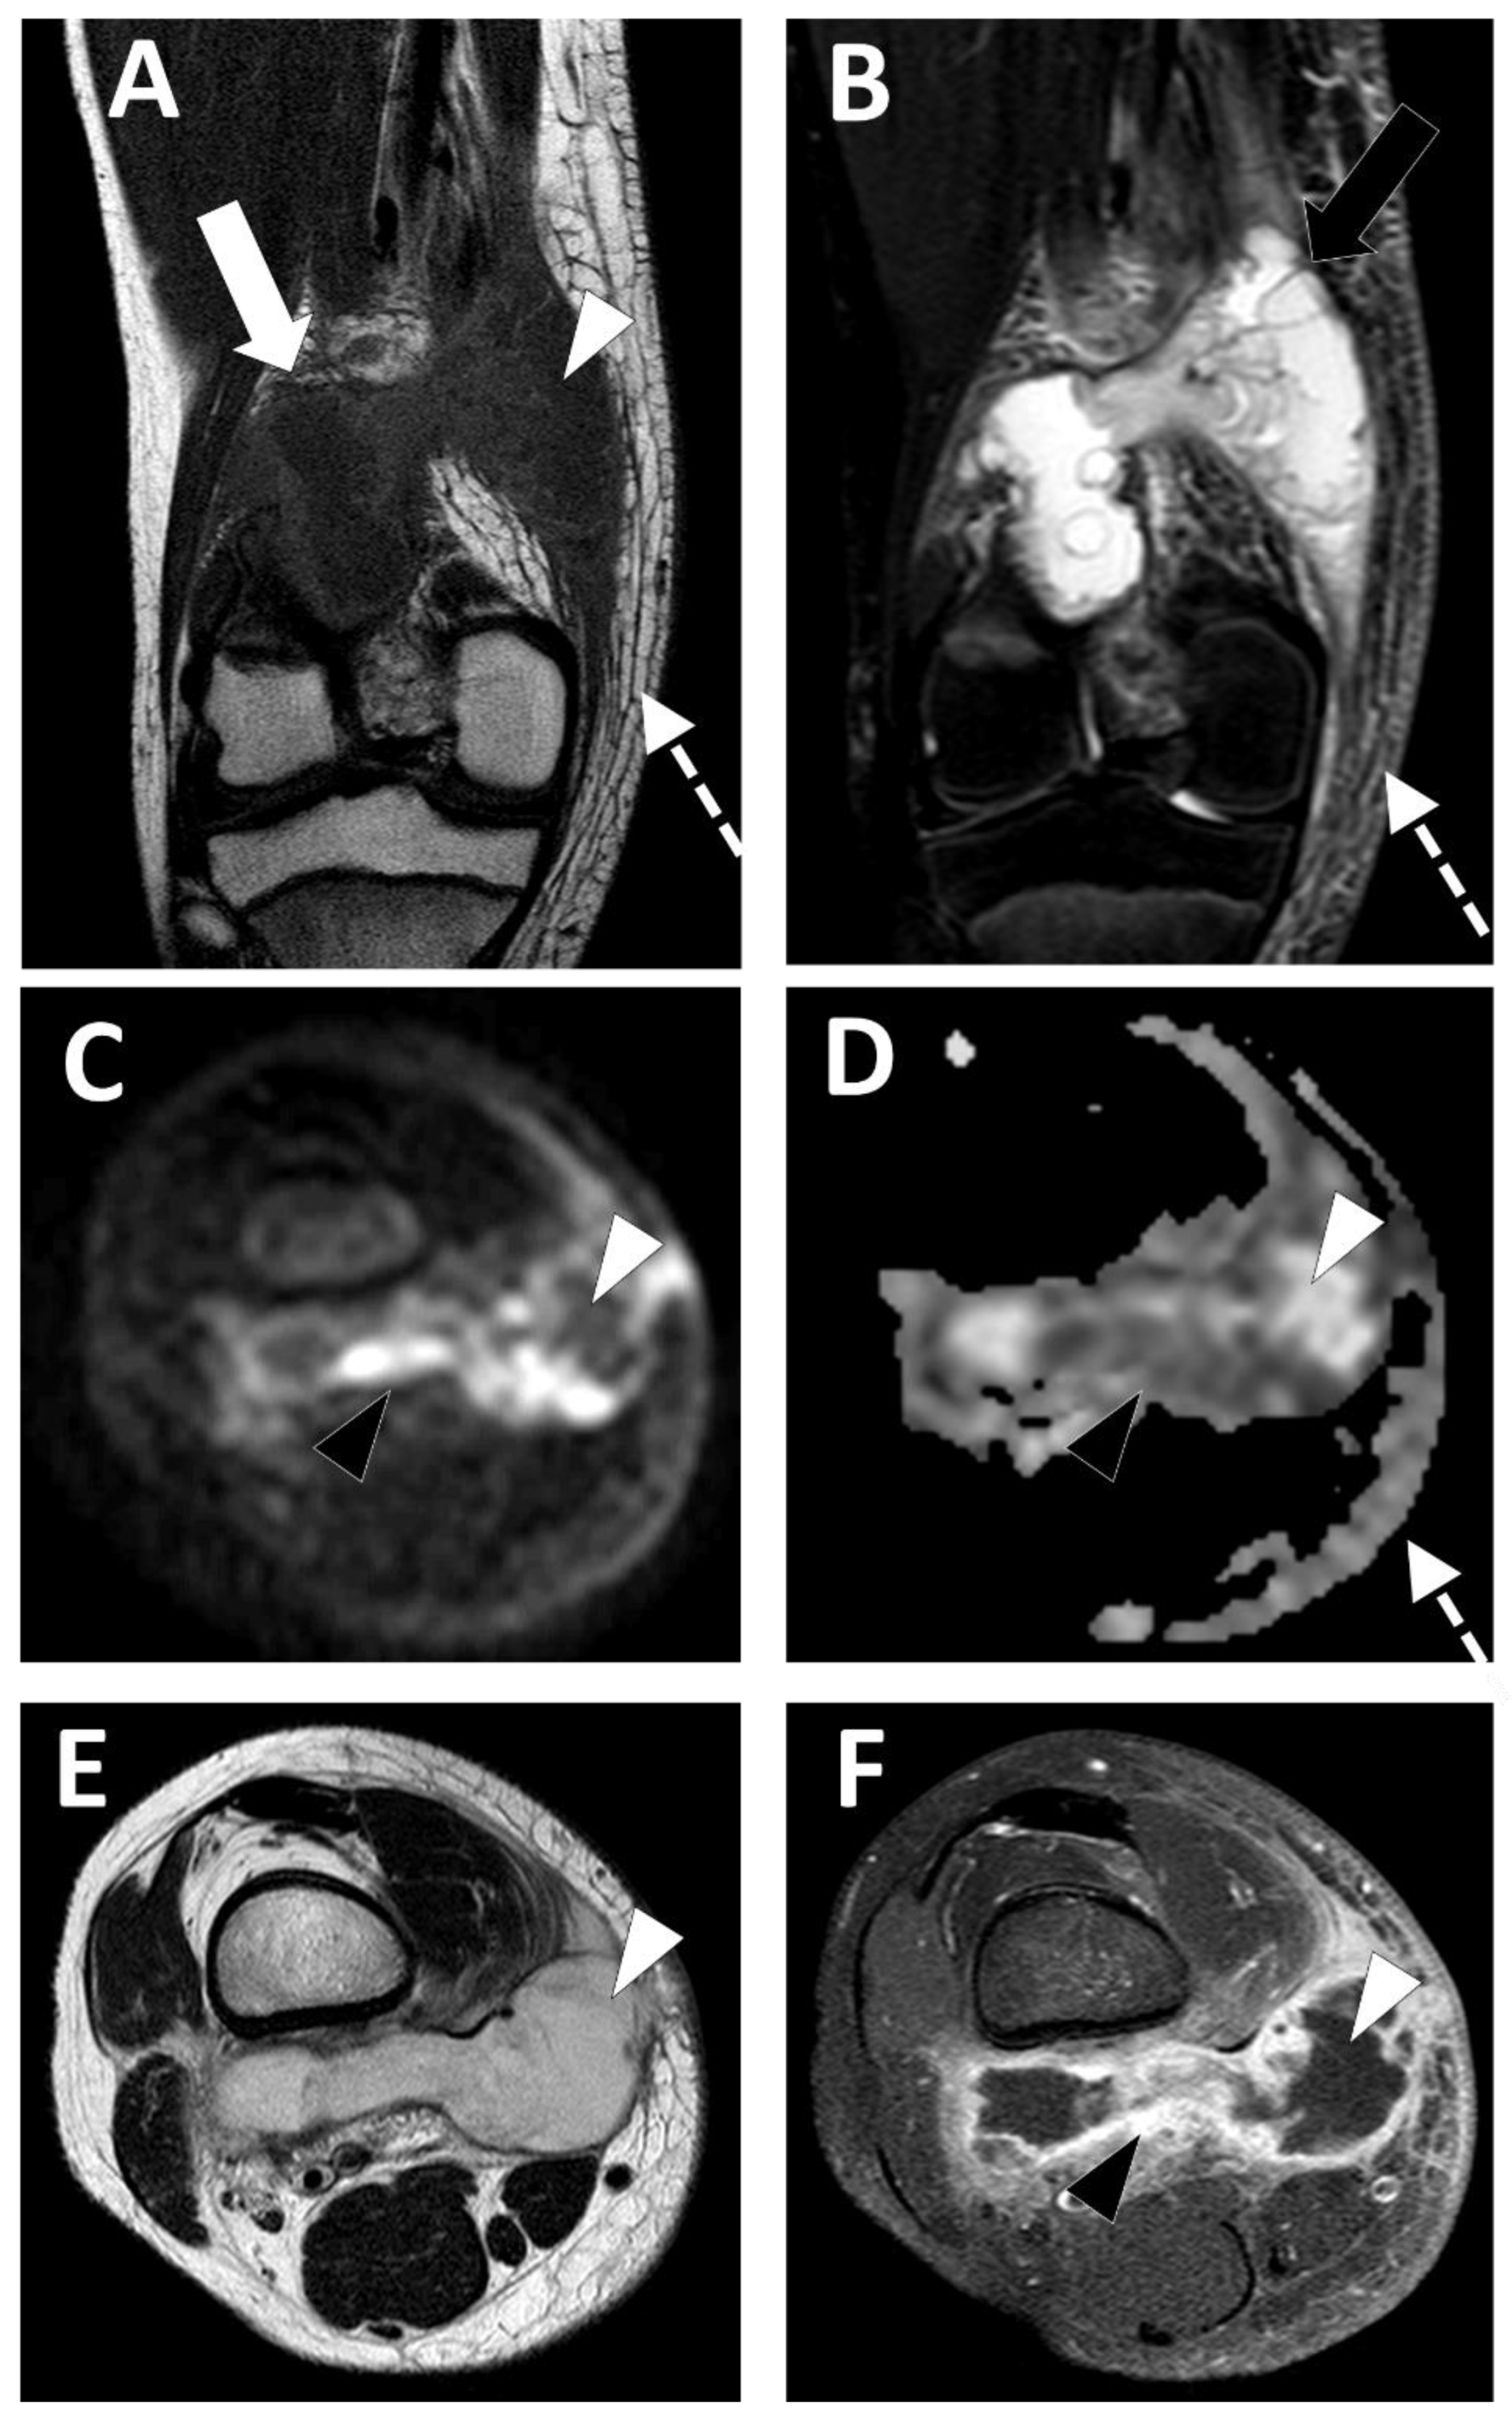

2.3. Soft-Tissue Foreign Body

- Del Cura, J.L.; Aza, I.; Zabala, R.M.; Sarabia, M.; Korta, I. US-guided localization and removal of soft-tissue foreign bodies. Radiographics 2020, 40, 1188–1195. [Google Scholar] [CrossRef]

- Ipaktchi, K.; Demars, A.; Park, J.; Ciarallo, C.; Livermore, M.; Banegas, R. Retained palmar foreign body presenting as a late hand infection: Proposed diagnostic algorithm to detect radiolucent objects. Patient Saf. Surg. 2013, 7, 25. [Google Scholar] [CrossRef]

- Davae, K.C.; Sofka, C.M.; DiCarlo, E.; Adler, R.S. Value of power doppler imaging and the hypoechoic halo in the sonographic detection of foreign bodies: Correlation with histopathologic findings. J. Ultrasound Med. 2003, 22, 1309–1313; quiz 1314–1316. [Google Scholar] [CrossRef] [PubMed]